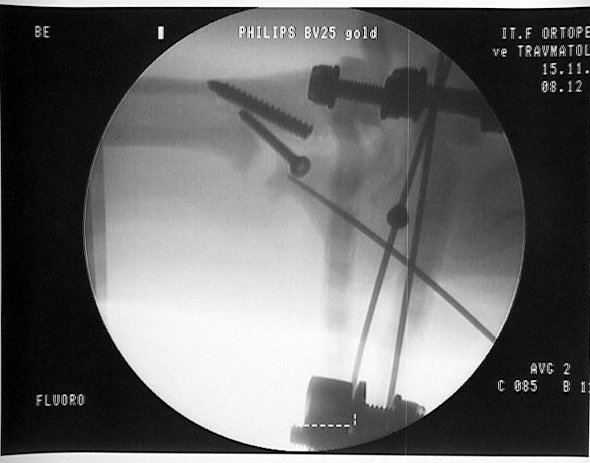

Vaka 2